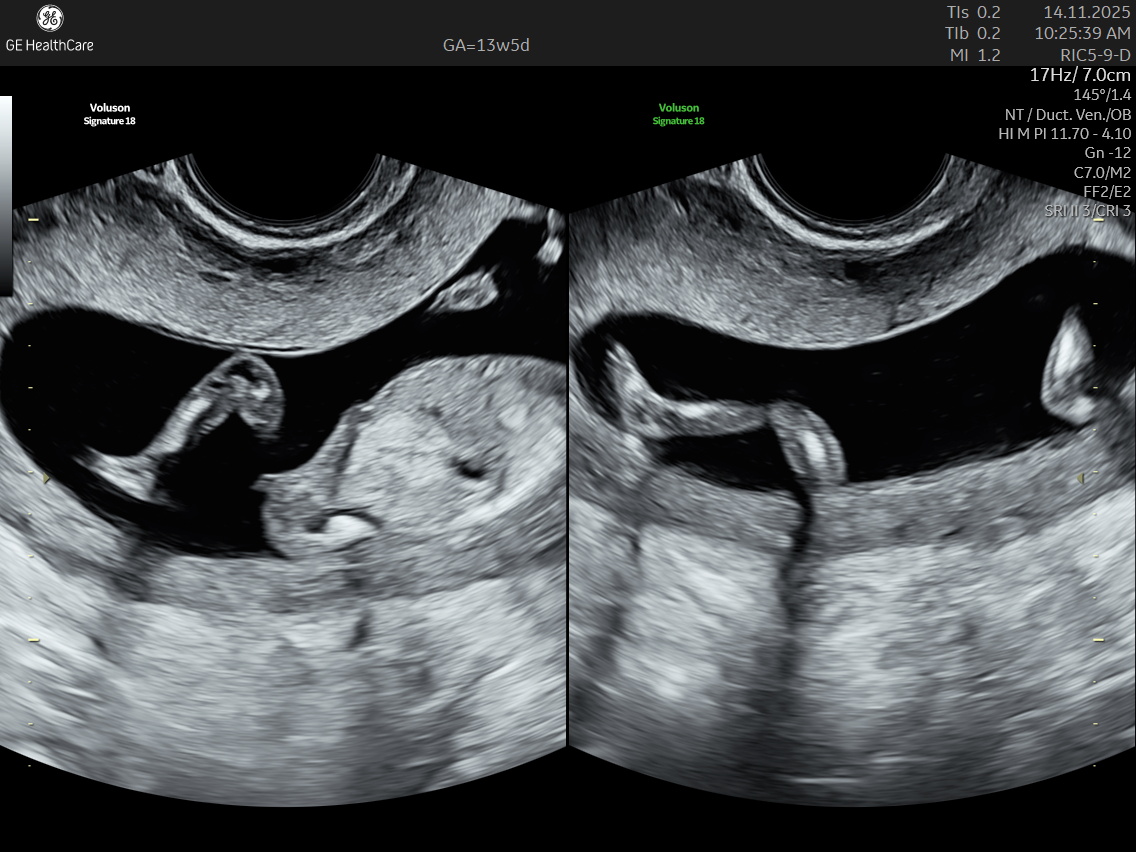

The NT scan is a non-invasive ultrasound examination conducted in the first trimester (12–13 weeks). It measures the nuchal translucency (the fluid at the back of the fetus’s neck) and combines it with the maternal blood test for a detailed risk profile. NT Scan is an important early screening test for Down syndrome (Trisomy 21), Edwards syndrome (Trisomy 18), and Patau syndrome (Trisomy 13).

Although the NT scan is mainly a screening tool and not diagnostic on its own, it can identify about 50% of major fetal abnormalities when combined with other assessments like blood tests and detailed ultrasound. The scan also helps to screen some basic anatomical structures during the first trimester, especially the fetal heart anatomy, brain, face, spine, stomach, abdominal wall, kidneys, bladder, and extremities to varying degrees depending on gestational age and maternal factors.